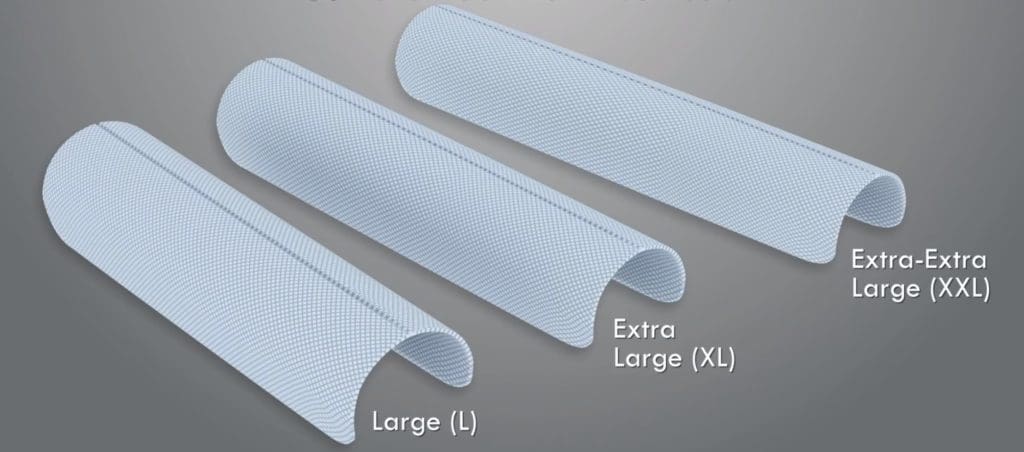

من ناحية أخرى ، بينوما (Penuma) عبارة عن غرسة سيليكون. يتم إدخال هذا الزرع في القضيب من خلال شق يتم إجراؤه عادةً في قاعدة القضيب. يمكن أن تأتي غرسات بينوما (Penuma) بثلاثة أحجام وقد تساعد في زيادة الطول والعرض. تتضمن بعض متطلبات جراحة بينوما (Penuma) وجود قضيب مختون كامل الشفاء وعدم وجود عمليات جراحية سابقة لتحسين الذكر ، بالإضافة إلى توصيات أخرى مثل الصحة العامة والتوقعات الواقعية للنتائج.

نحن نعلم ما الذي ربما تتساءل عنه: كم عدد الأحجام المعروضة؟ حسنًا ، الجواب واحد.